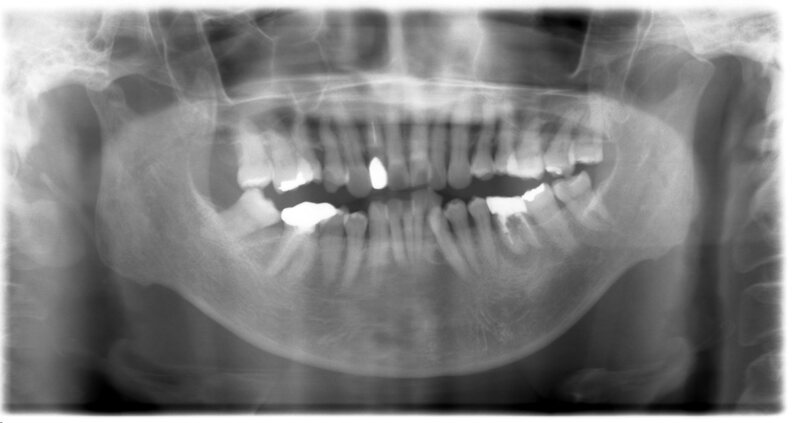

親知らずの症例一覧

現在の治療費と異なる場合がございます。

最新の治療費については、医院へ直接お問合せください。